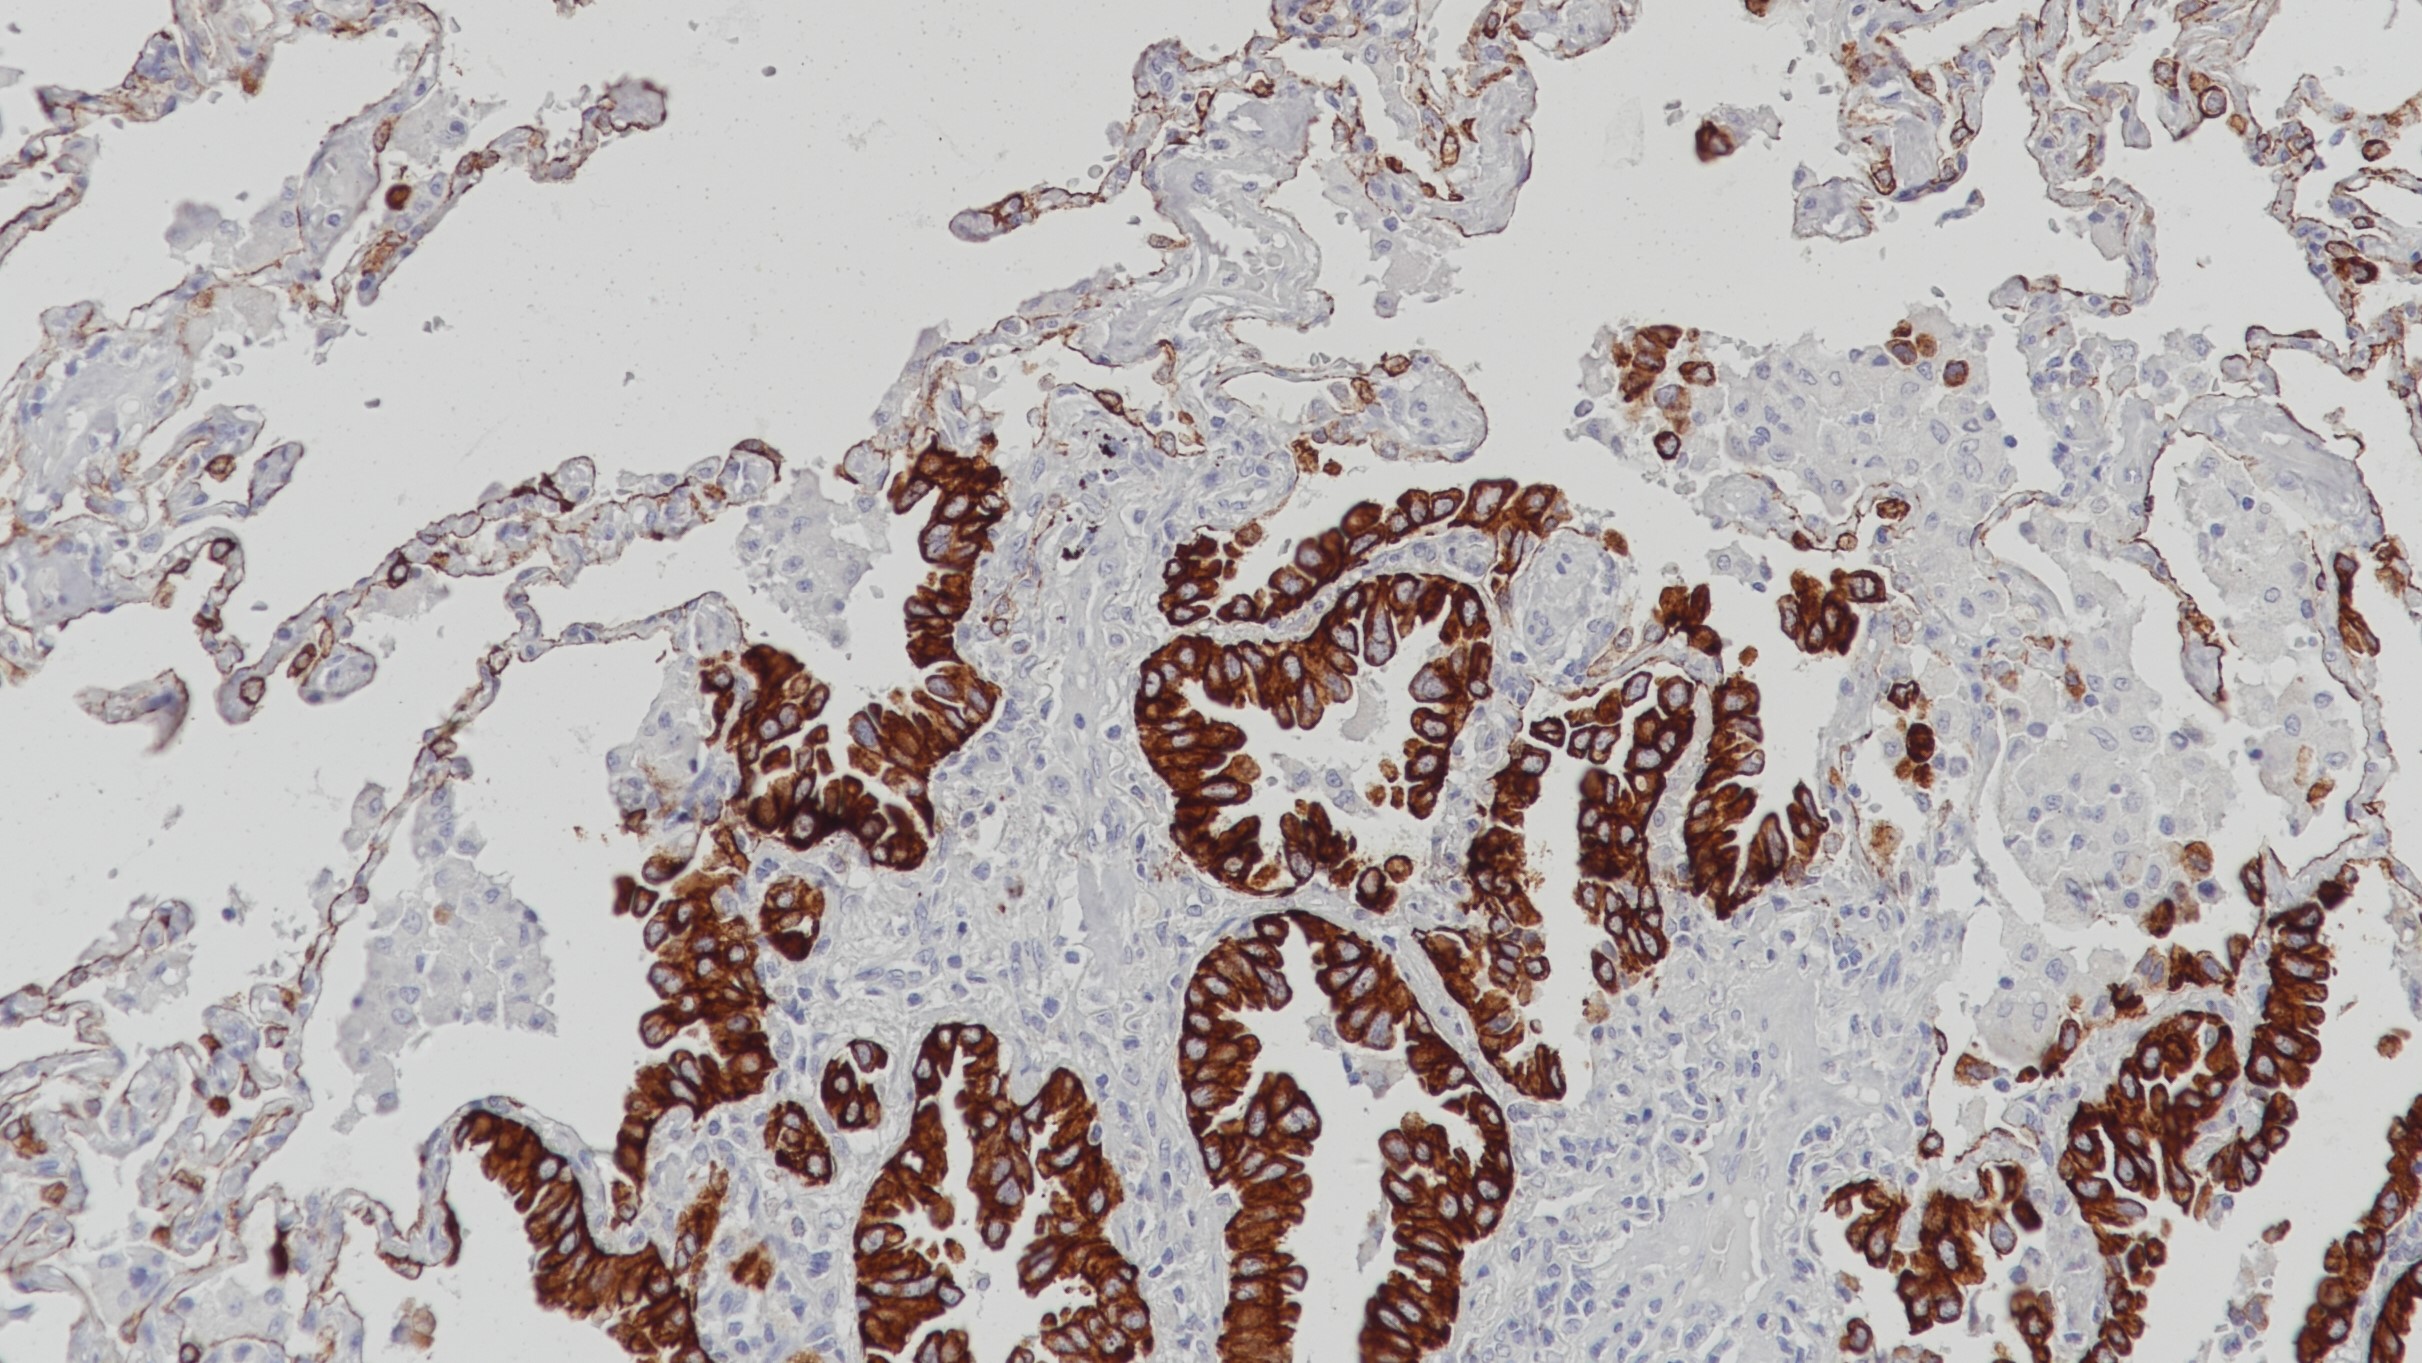

Cytokeratin 7(CK7) 重组兔单克隆抗体

CK7是一种由KRT7基因编码合成的蛋白,通常和CK19成对出现。CK7在腺上皮和导管上皮中表达,如肺、乳腺、膀胱等,而在大部分消化道上皮、前列腺、肝细胞以及鳞状上皮中染色阴性。肿瘤组织中,大肠癌、前列腺癌以及鳞状上皮癌表现为CK7-。在临床上,CK7通常与CK20以及CDX-2一起用于卵巢癌、肺癌、乳腺癌(CK7+)以及大肠癌(CK7-)的诊断。

阳性对照

乳腺癌